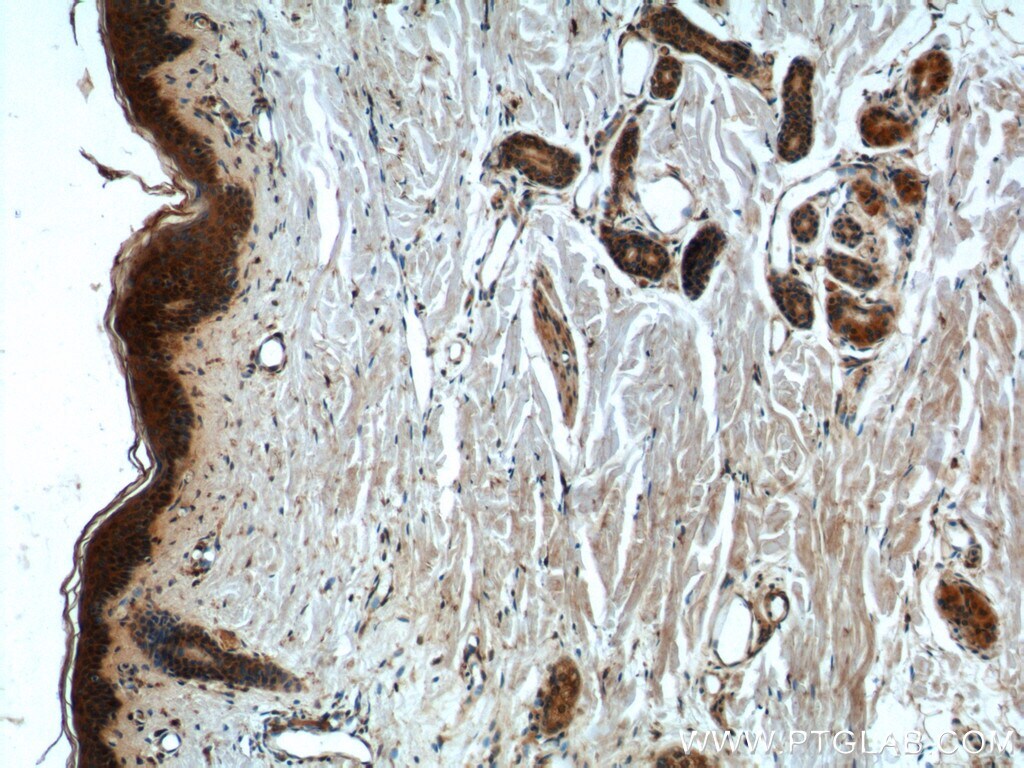

- Submitted by

- Main image

- Experimental details

- Immunohistochemistry of paraffin-embedded human testis tissue slide using 21869-1-AP ( CCHCR1 Antibody) at dilution of 1:50 (under 40x lens).